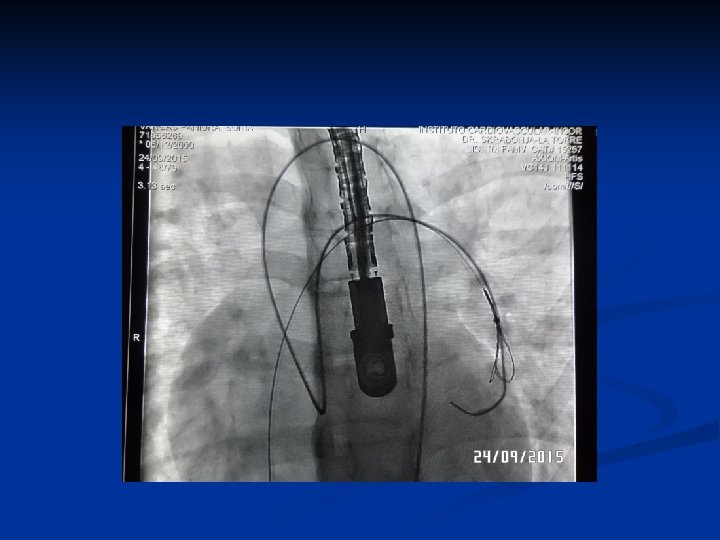

Cat. Diagnostico

Creación Sist. Arterio-Venoso

Control Cierre